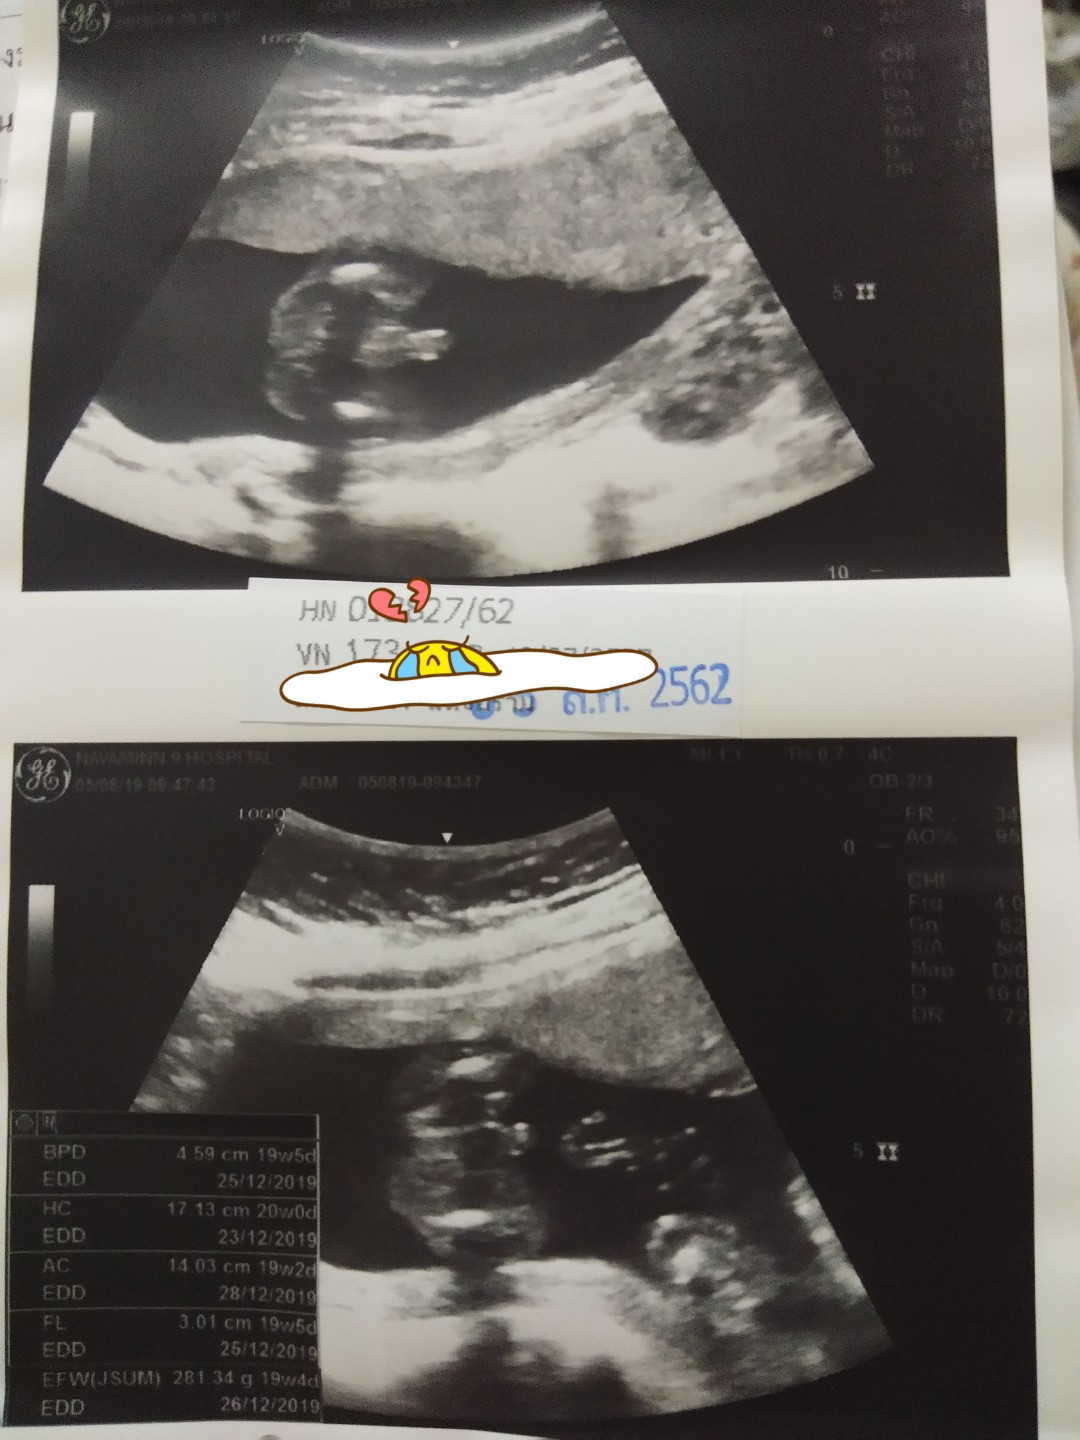

ขอดูใบซาวด์แม่เพศ ชาย หญิง หน่อยค่ะ

เจ้าจู๋น้อย

ผู้ชายจ้า

เพศชายจ้า